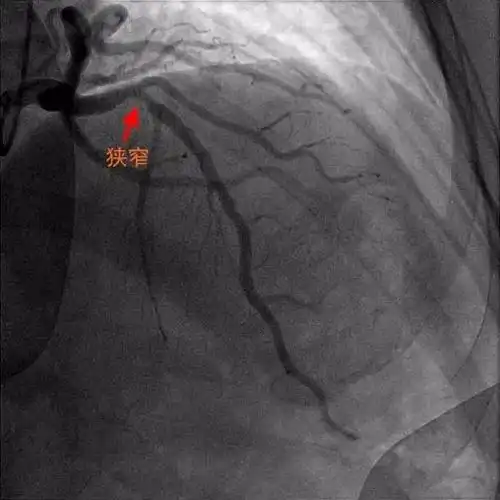

冠脉造影结果显示血管狭窄达75以上就要放支架心内科医生说未必